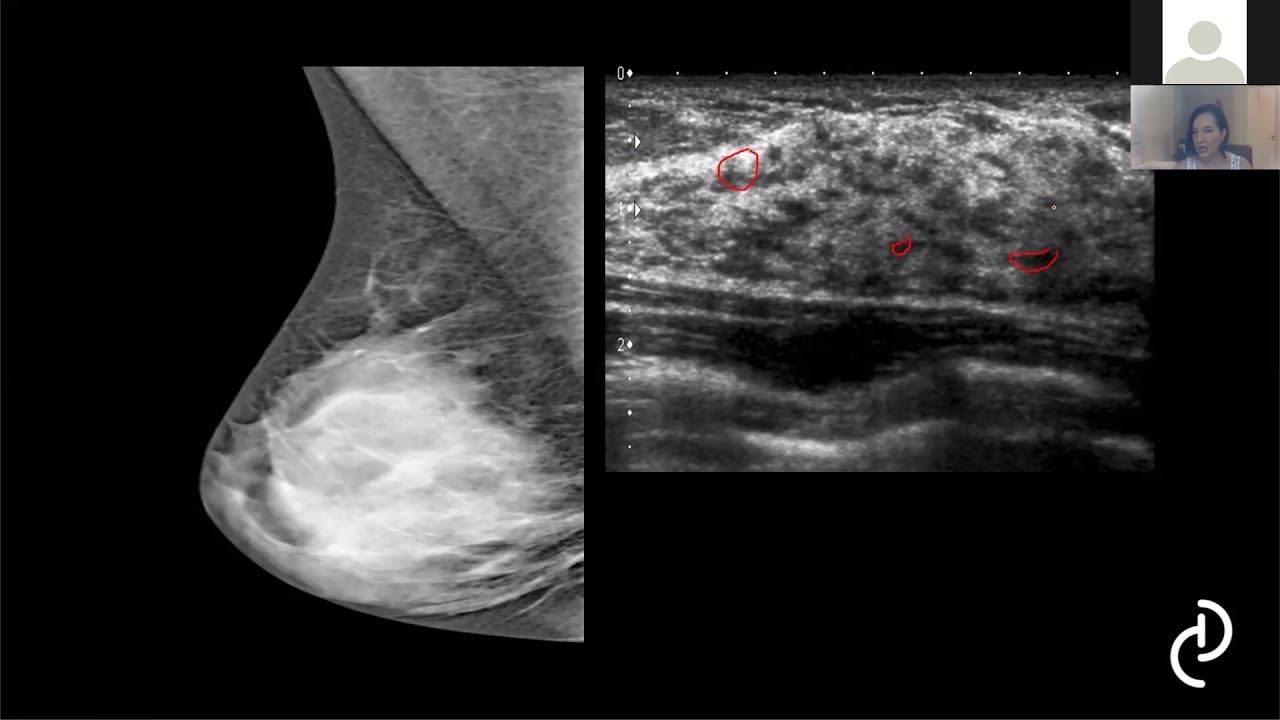

as sequências para que elas servem então a ideia da aula quando eu ia dizer gente conversou vai fazer uma coisa básica é que seja acessível para vários tipos de profissionais não só radiologia estejam iniciando a prática da ressonância como também o Vasco e eu já colorista saber reconhecer o laudo da paciência é essa vamos lá É a ressonância magnética diferente da mamografia e ultrassom ela é um método de imagem com técnica funcional ela consegue detectar as lesões através do real que causado pelo contraste endovenoso então assim a gente precisa do Contagem já é injetado o

contraste na paciente esse contraste vai aumentar o sinal é da lesão EA gente vai conseguir reconhecer pela ressonância e ele dá certo essas lesões através do aumento da densidade a densidade da Permeabilidade vascular então princípio da ressonância aqui você temos uma lesão essa lesão ela vai ter vascularizado e quanto mais suspeita ou seja uma lesão maligna mais vasos ela vai ter então tumor ele vai liberar substâncias que vão promover o aumento dessa perna habilidade vascular vai formar novos vasos para no trio e o contraste vai entrar lá naquela lesão vai aumentar o sinal e a

gente vai detectar através do real e por que isso acontece o que Acontece a Amanda ela tem a vascularização própria mas a lesão ela vai ter uma vascularização maior Então vai chegar contraste primeiro na lesão do que no parente mas a gente vai poder diferenciar O que seria uma lesão do que seria o parente em uma normal da mama é assim que a gente deve certa as lesões através da ressonância de mama é a ressonância ela me não tem a sua sensibilidade reduzida pela densidade do parênquima mamário diferente da Mamografia que a densidade ela é